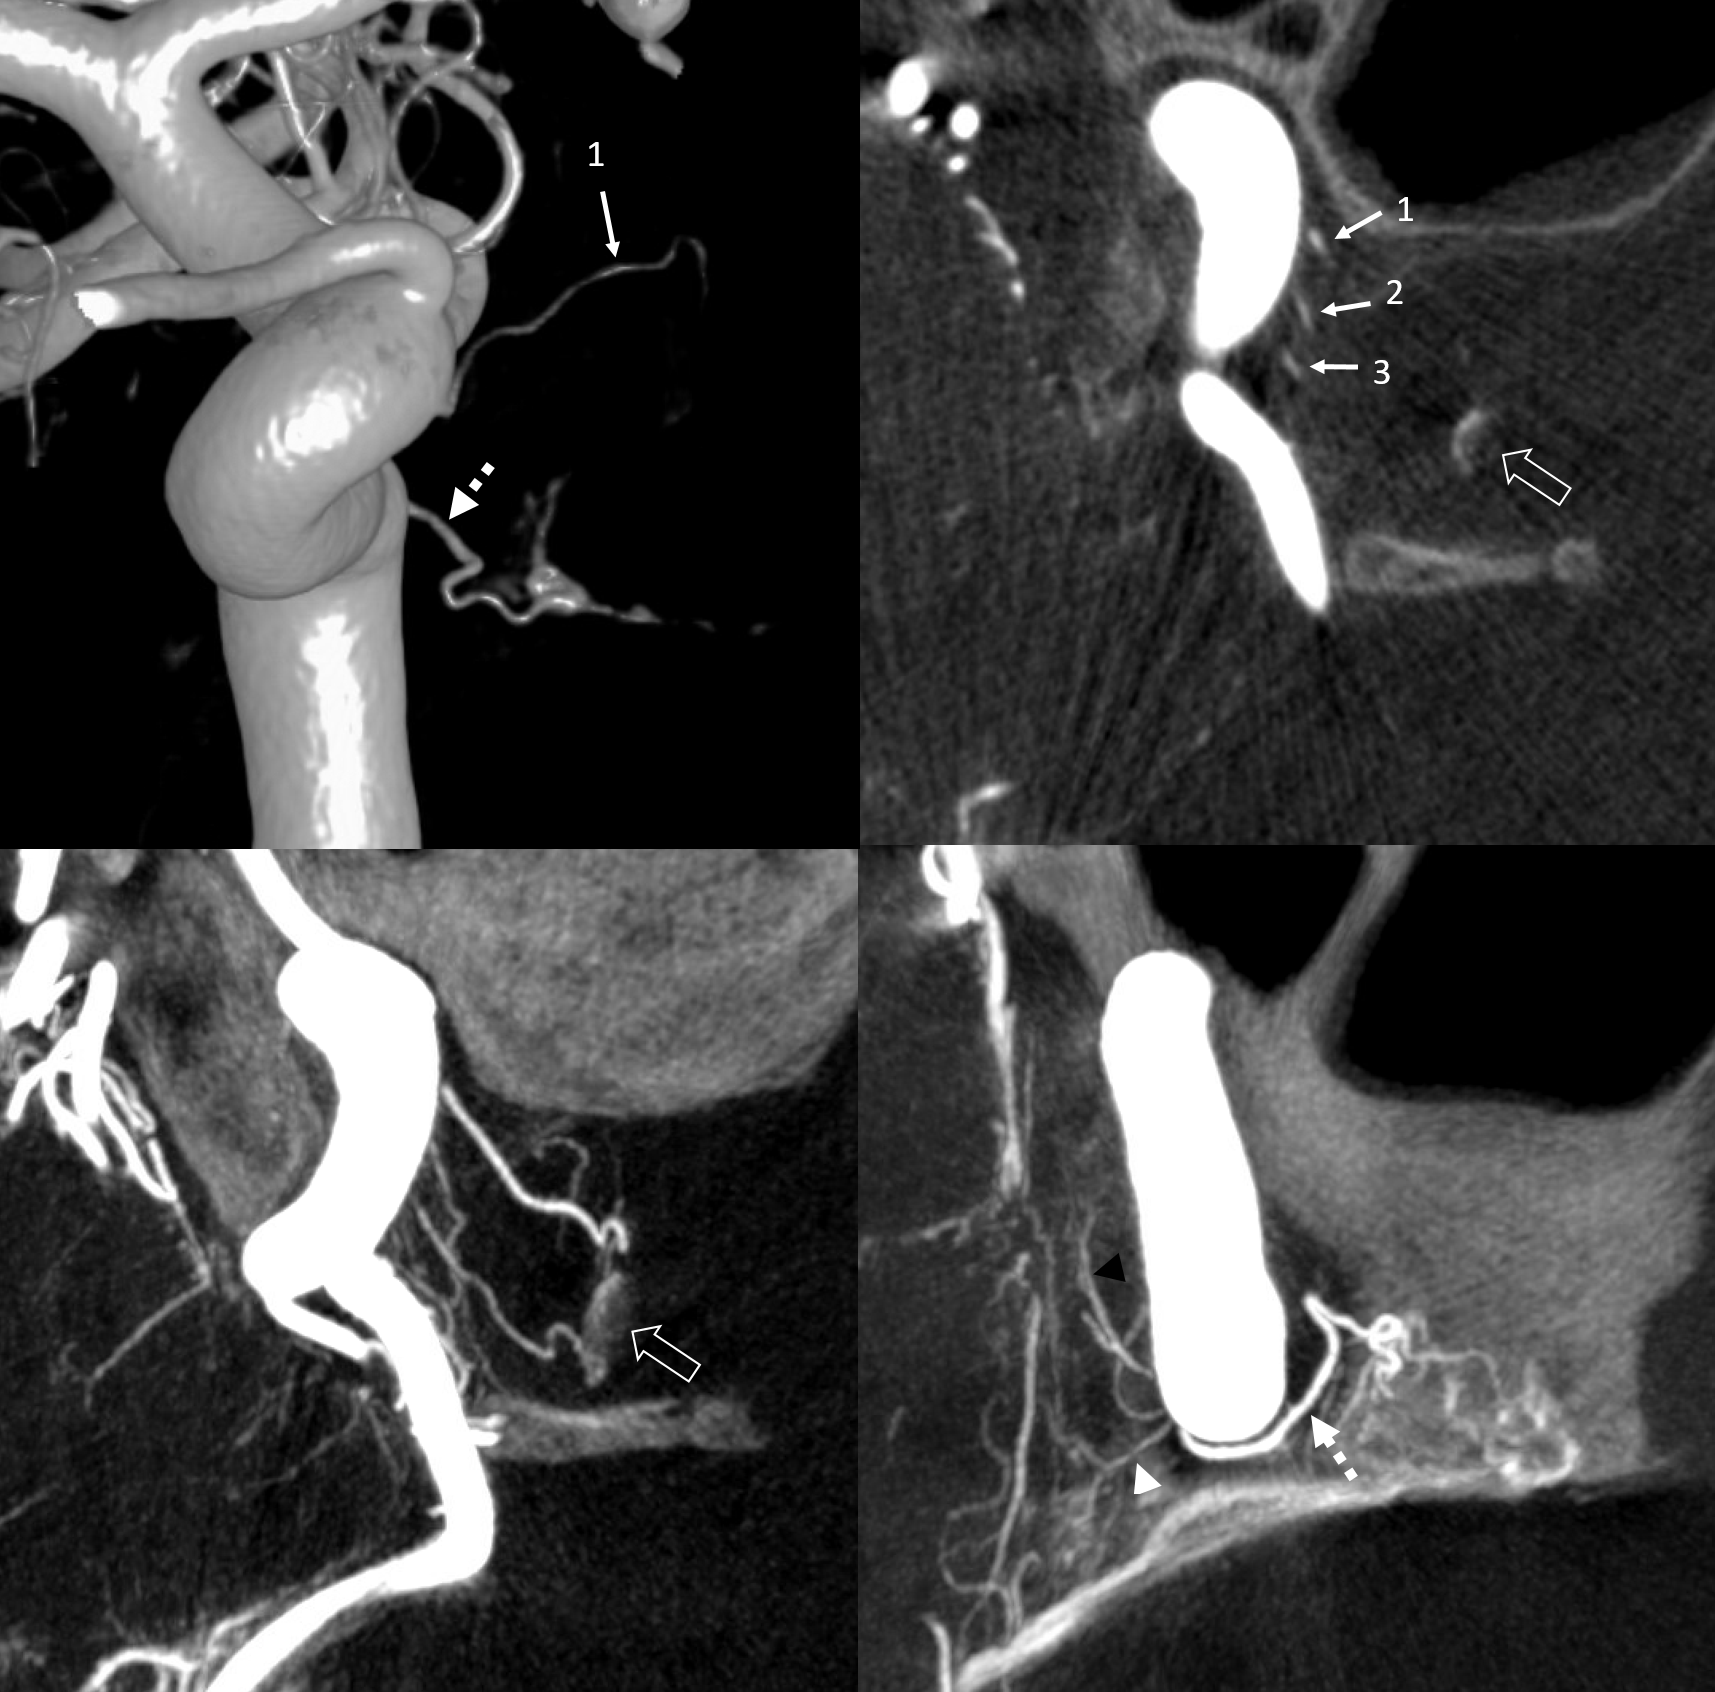

Supply of the Hypophysis and Balance

As always neuroangio is about balance. There may be one or more superior hypophyseal arteries. Usually one is visible by cone beam/flat panel CT. Sometimes more than two. Here there are 3. Nicely shown is supply of the stalk (open arrow). There is also likely contribution to the optic chiasm, which is of course very important. The inferior hypophyseal branches (dashed arrow) from the MHT support the posterior pituitary. The ILT is hypoplastic, with lateral branches of the MHT (white arrowhead) heading towards the meckel cave and the recurrent branch along the tentorial edge (black arrowhead) supplying territory normally done by the ILT

What supplies the bulk of optic nerve? Central Retinal artery is for the distal portion of nerve and retina. What about the rest — intracranial, intracanalicular, proximal intraconal segments? The answer is not clear (let me know if you do), but i believe the bulk of it comes from the superior hypophyseals. It is probably in balance with the recurrent branch of the central retinal artery. Below is an example of an especially prominent proximal-most superior hypophyseal (arrows) supplying the pituitary stalks and optic nerve in the canalicular and intracranial locations. Note how well one can see the branch in coronal view (bottom left image). In this case there are two large superior hypophyseals — the more distal one (dashed arrows) supplies predominantly the pituitary stalk. The inferior hypophyseal artery is marked by arrowhead. Lower right image is coronal.

VR — the anterior-most branch of the superior hypophyseals is usually the largest (arrow). The others are too small to see on a VR image

MIPS. The anterior, proximal-most branch (arrow) tends to supply the optic nerve (white oval), while the more posterior branches (dashed arrows), when present, supply more posterior structures such as chiasm and tract (dashed oval)

More Optic Nerve Supply — its easier to see on MIPS, but with the right windowing, and stereo, VR imaging is also possible. Here, there are 3 superior hypophyseals seen. The anterior-most (arrow) is usually the largest, suppling the optic nerve (dashed arrow) and chiasm (ball arrow). The middle and posterior hypophyseals (arrowheads) supply the stalk.

Stereo of VR image. Same arrows. The stalk is open arrow.

Another patient — also 3 arteries. Cave origin of the anterior-most (arrows) one. The middle one (arrowheads) also supplies the optic nerve. The posterior one (dashed arrows) is for the stalk.

VR images (stereo pair on bottom). The cave origin of the anterior branch is most beautifully seen in the upper right image.